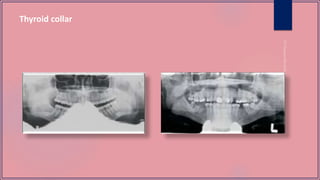

 Make the patient wear a lead apron without a thyroid collar, and remove all objects from the head which will interfere

Thyroid collar